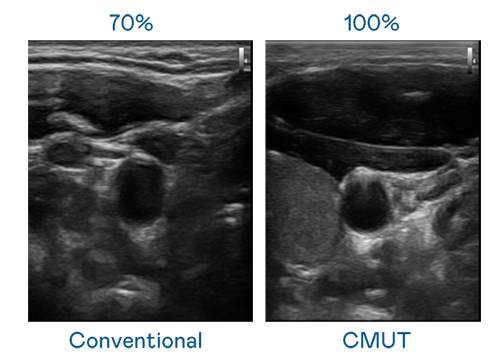

CMUT 技术是一种用电容式微机电元件来产生超音波讯号的技术。与传统 PZT 压电式技术相比,CMUT 频宽增加 30%,更宽频的超音波讯号让影像解析度大幅提升,是实现高影像品质医疗超音波扫描、促进精准医疗发展的关键技术。

大频宽带来超清晰影像

超音波影像的解析度高低,首先取决于探头能发出的讯号频宽。红桃国际 CMUT 可提供高清晰的超音波讯号,提供高频宽、高灵敏度、影像纹理细节更高的超音波影像,协助医护人员缩短影像判读时间及利用精准的医疗影像进行诊断。